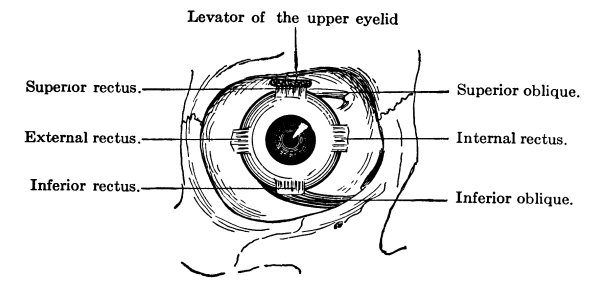

The Nose, 57—The Sense of Smell, 58—The Mouth, 59—The Hyoid Bone, 60—The Teeth, 60—The Sense of Taste, 61—Salivary Glands, 61—The Tonsils, 62—The Ear, 63—Eustachian Tubes, 63—Sensation of Hearing, 65—The Eye, 66—Lachrymal Gland, 68—Coats of the Eye, 68—Light Rays and Sight, 70—Accommodation, 72—Color Perception, 73. |